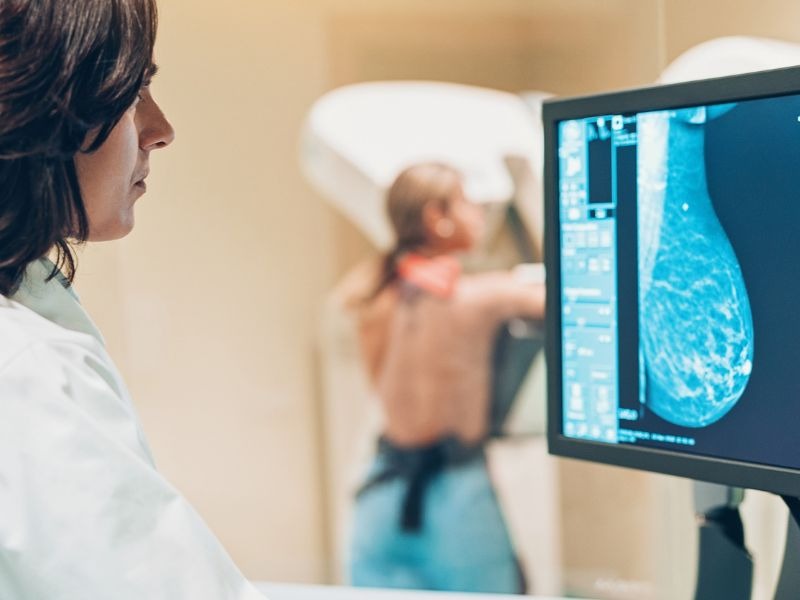

Chụp Mammography được chỉ định trong quy trình tầm soát ung thư vú thường quy

4. Quy trình chụp Mammography diễn ra như thế nào?

Quy trình chụp Mammography được thực hiện như sau:

Kỹ thuật viên X-quang sẽ đặt vú của bạn vào thiết bị chụp Mammography. Vú sẽ được đặt trên một bề mặt đỡ đặc biệt và sau đó được ép lại bằng một tấm nhựa trong suốt. Kỹ thuật viên sẽ nén vú một cách từ từ, sau đó thực hiện chụp. Trong khi chụp, bạn cần giữ yên cơ thể và có thể được yêu cầu nín thở trong vài giây. Sau đó kỹ thuật viên hỗ trợ bạn thay đổi tư thế giữa các lần chụp khác nhau.

Toàn bộ quy trình chụp Mammography thường kéo dài khoảng 30 phút. Sau đó, bác sĩ chẩn đoán hình ảnh sẽ đánh giá và gửi phân tích chi tiết đến bác sĩ của bạn để trao đổi.

Toàn bộ quy trình chụp Mammography thường kéo dài khoảng 30 phút.